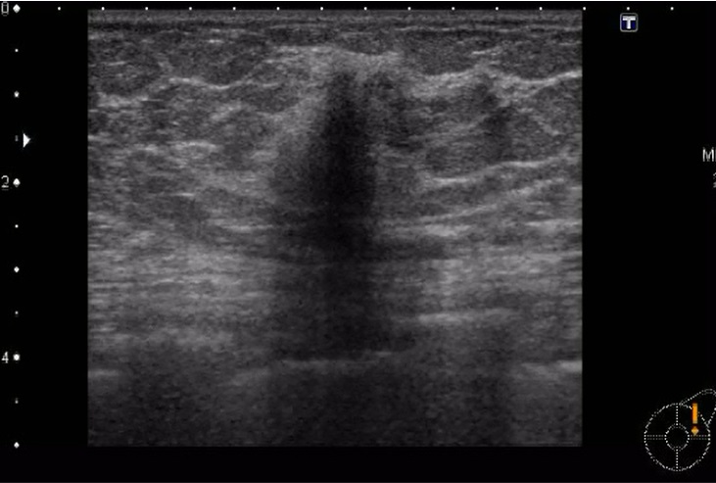

60代 女性

乳房超音波検査を行った。そのときの超音波画像(動画1枚、静止画1枚)を示す。

乳房超音波検査

静止画(No22-23_1)

設問22

超音波画像をみて、正しいのはどれか。

① 境界明瞭粗ぞうの低エコー腫瘤

② 内部エコー不均質の高エコー腫瘤

③ 形状不整形な縦横比の小さな腫瘤

④ 形状分葉形の後方エコー不変の腫瘤

⑤ 後方エコー減弱、境界部高エコー像がみられる腫瘤

設問23

画像の病変で考えられるのはどれか。

① 嚢胞

② 線維腺腫

③ 葉状腫瘍

④ 浸潤性乳管癌

⑤ 非浸潤性乳管癌